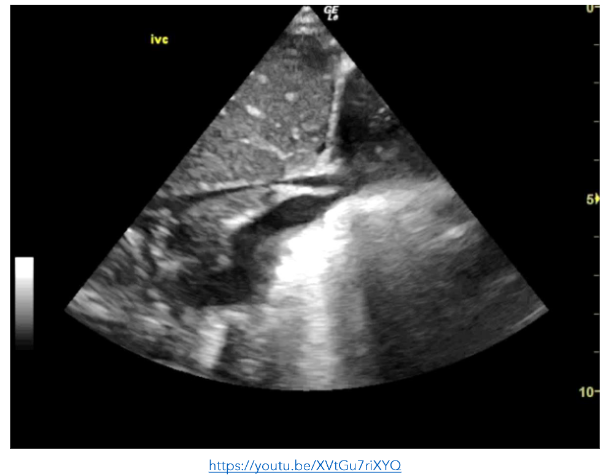

In an effort to guide both sepsis management and fluid resuscitation, POCE was performed which showed a hyper-dynamic left ventricle, a small pericardial effusion, and a collapsing inferior vena cava (IVC).

This supported the clinical requirement for further fluid resuscitation following the initial 20ml/kg bolus. Recurrent monitoring of left ventricular function and IVC collapsibility during inspiration were used as surrogates for the central venous pressure and intravascular volume.